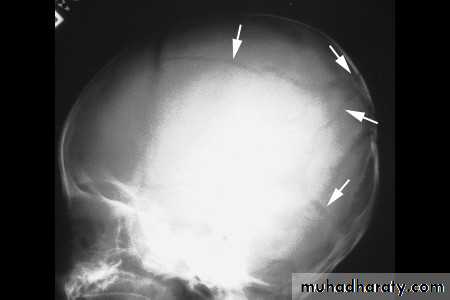

كسور الجمجمة، انظر الى الصورة القادمة

20 نيسان، 1315